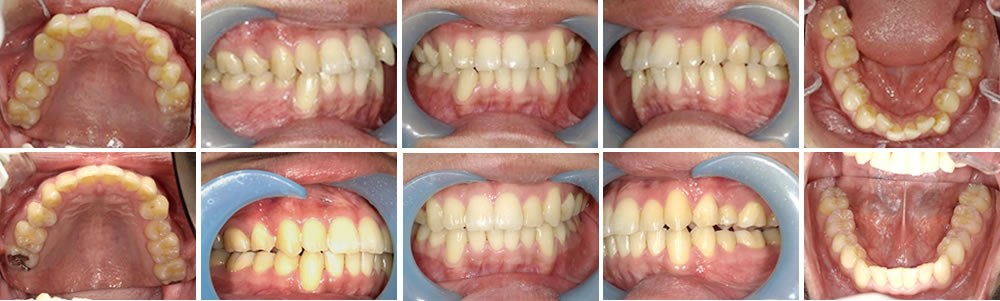

マウスピース矯正(インビザライン)で空隙・歯並びを改善した症例

年齢

20代

性別

女性

症例を見る

マウスピース矯正(インビザライン)で前歯の歯並びを改善した症例

30代

マウスピース矯正(インビザライン)で前歯の叢生を改善した症例

男性